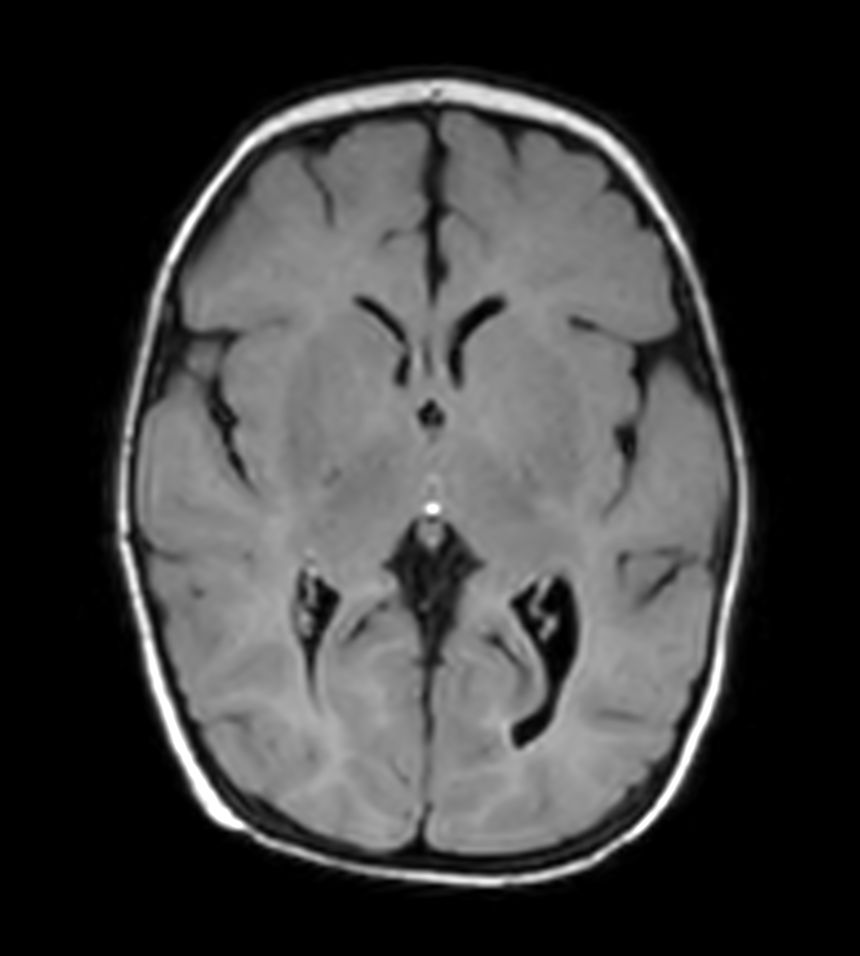

Axial T2w FLAIR with ComforTone